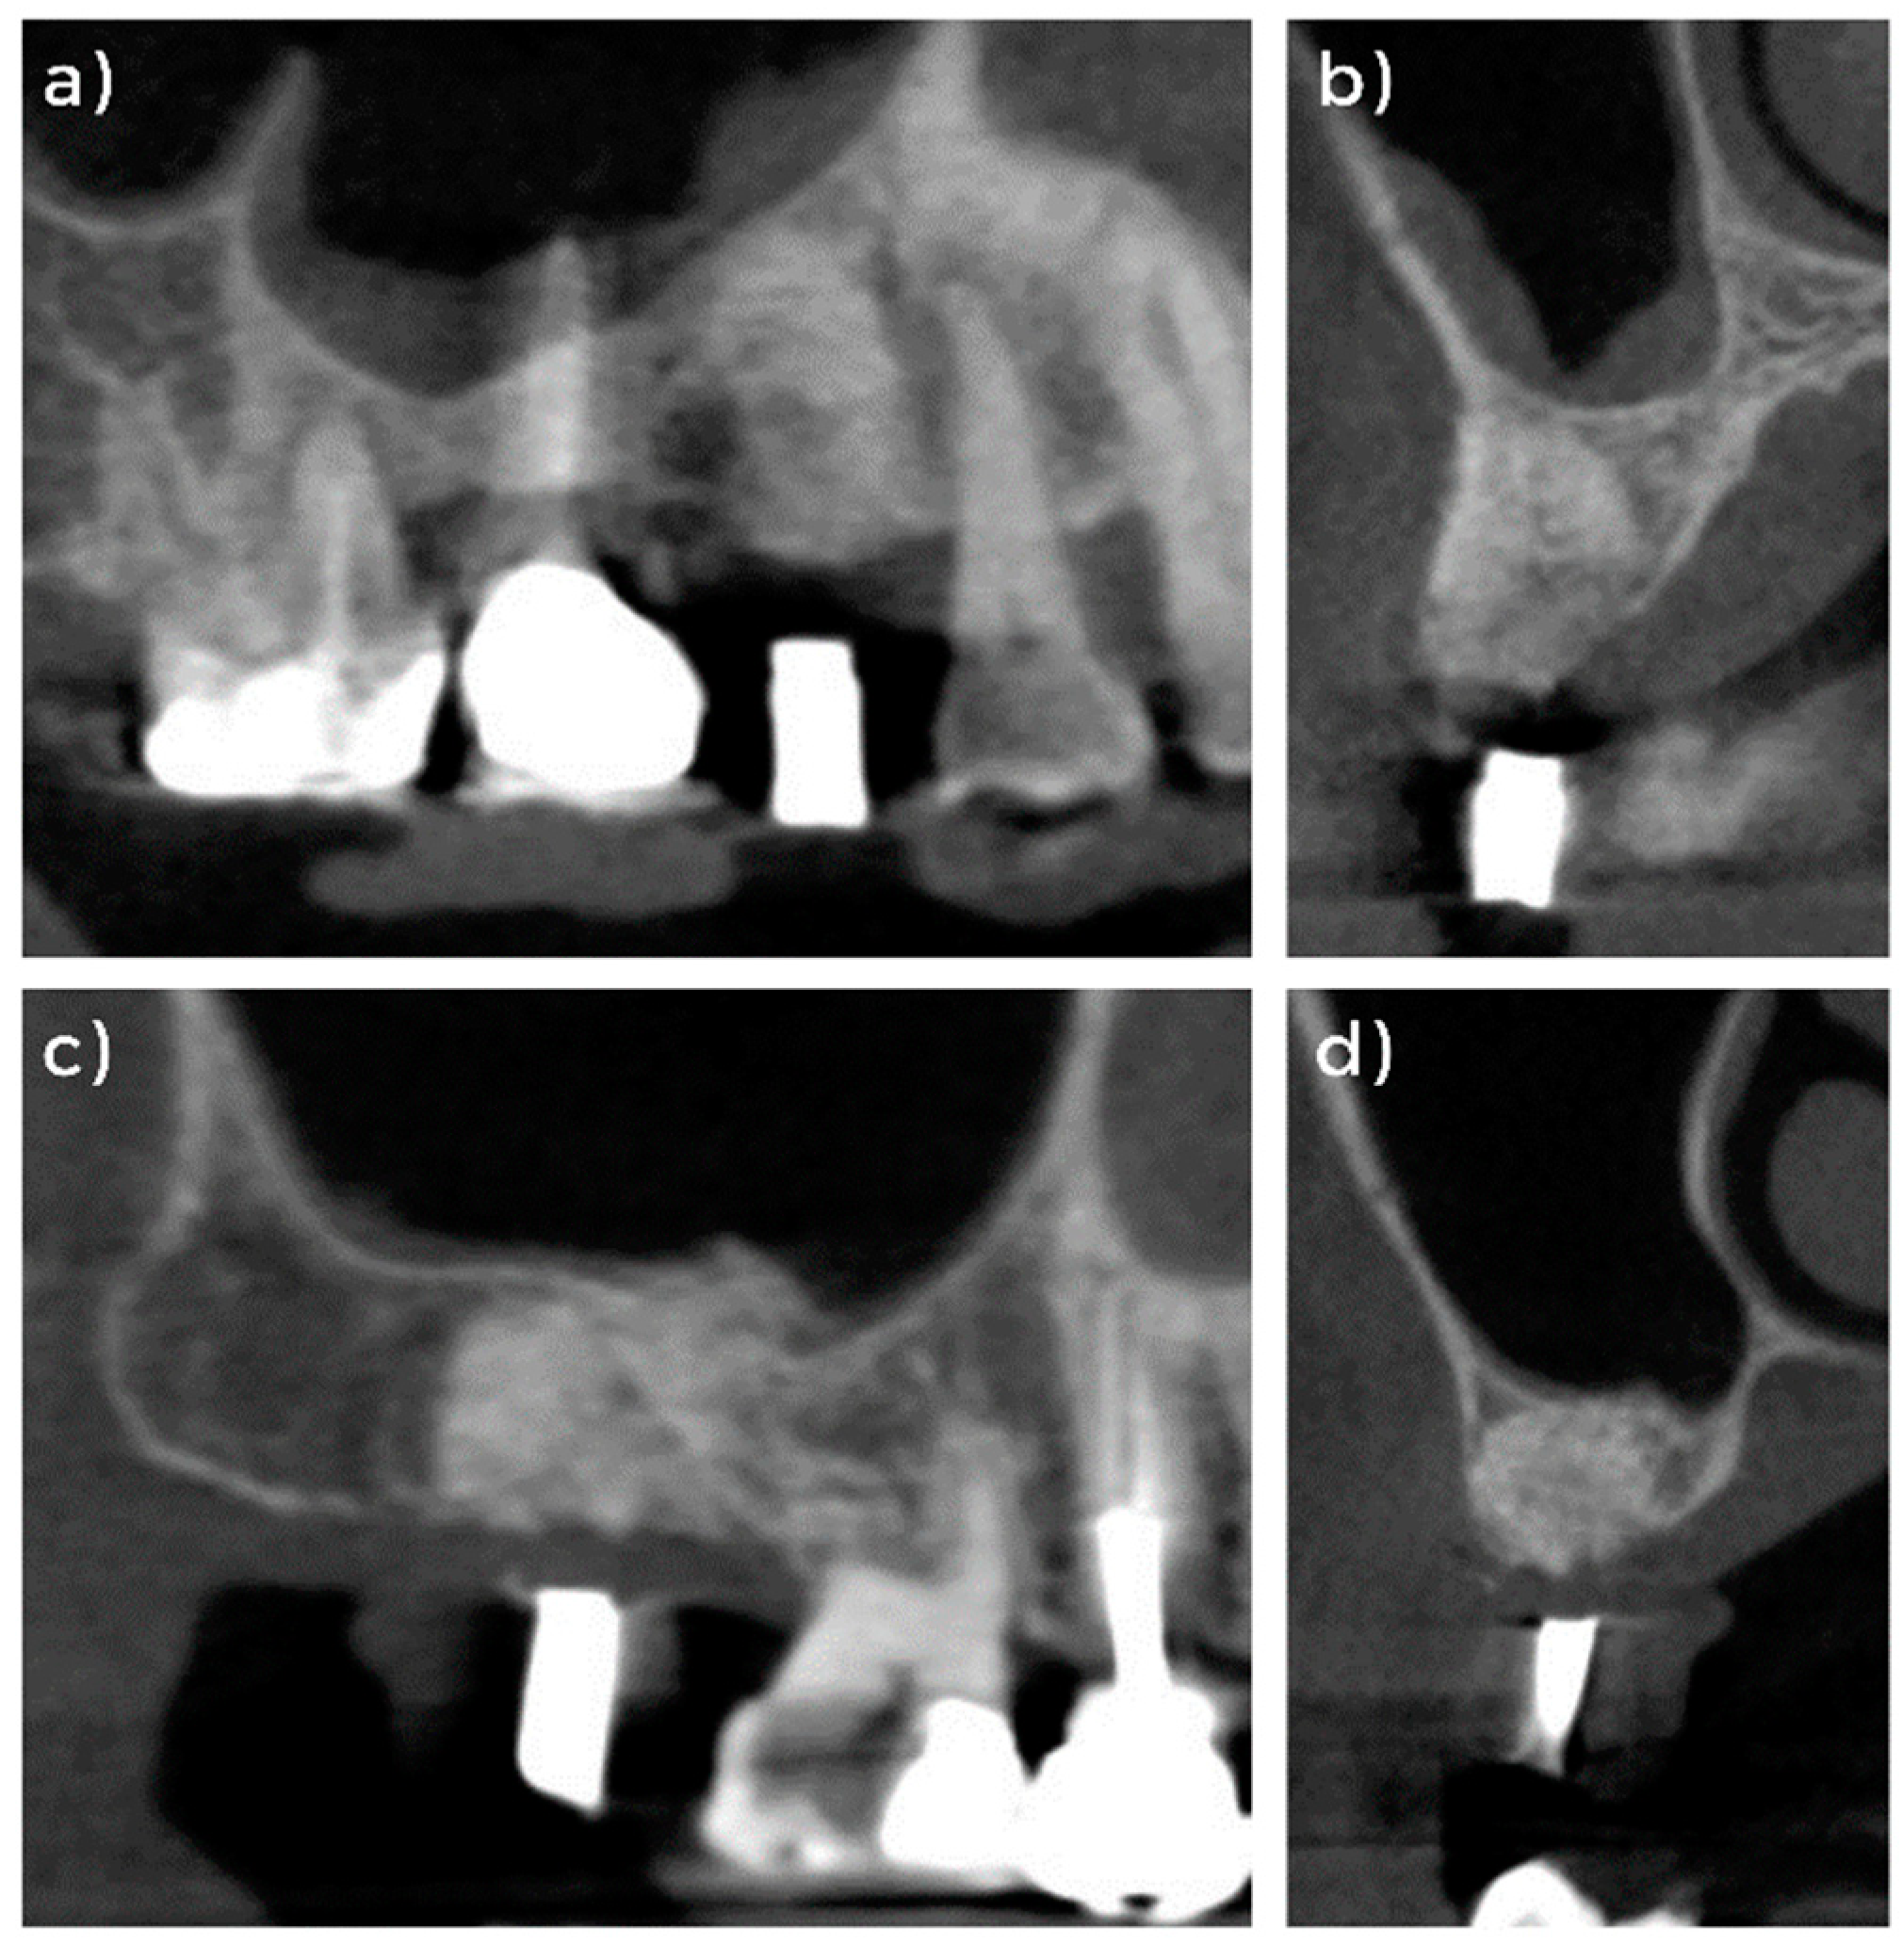

3.1. Clinical and Radiographical Evaluation